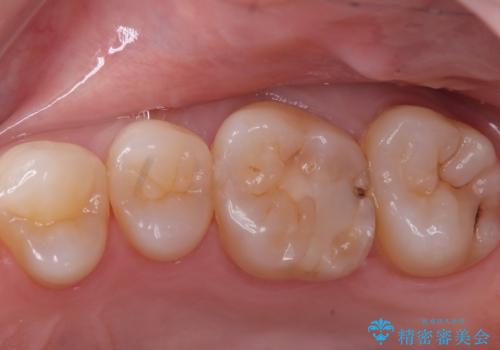

- 主訴:舌で触ったら歯に穴が空いていた。しみたりはしていない。

左上6番目の歯の噛む面に穴が空いていました。穴自体は小さいものでしたが、歯の中で虫歯が広がっていることが確認でき、虫歯の大きさを考慮しインレーでのやり替えとなりました。

咬合面に穴が空き、歯の中でう蝕が広がっていました。この歯が過去に咬合面う蝕を経験しCR修復を受けていること、今回歯質とCRの境目からの二次う蝕になっていることを説明し、適合や材料安定性の良いセラミックインレーでのやり替えとなりました。